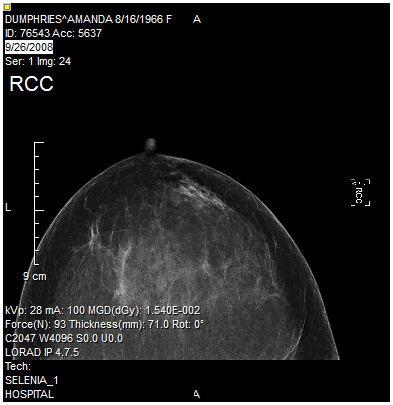

The Rotate Image tool will rotate an image by a user defined number of degrees. Clicking the Rotate Image icon opens the Rotate screen as shown below.

The Angle field denotes the angle of rotation to be applied to the desired image. The Direction of the rotation can be chosen by choosing the desired option. Once the desired values have been entered, clicking OK will apply the rotation to the selected image.

| Before | After |

|---|---|

![]() | ![]() |